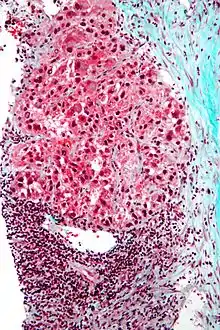

Pathology

Macroscopically, liver cancer appears as a nodular or infiltrative tumor. The nodular type may be solitary (large mass) or multiple (when developed as a complication of cirrhosis). Tumor nodules are round to oval, gray or green (if the tumor produces bile), well circumscribed but not encapsulated. The diffuse type is poorly circumscribed and infiltrates the portal veins, or the hepatic veins (rarely).[17]

Microscopically, the four architectural and cytological types (patterns) of hepatocellular carcinoma are: fibrolamellar, pseudoglandular (adenoid), pleomorphic (giant cell), and clear cell. In well-differentiated forms, tumor cells resemble hepatocytes, form trabeculae, cords, and nests, and may contain bile pigment in the cytoplasm. In poorly differentiated forms, malignant epithelial cells are discohesive, pleomorphic, anaplastic, and giant. The tumor has a scant stroma and central necrosis because of the poor vascularization.[41] A fifth form – lymphoepithelioma like hepatocellular carcinoma – has also been described.[42][43]